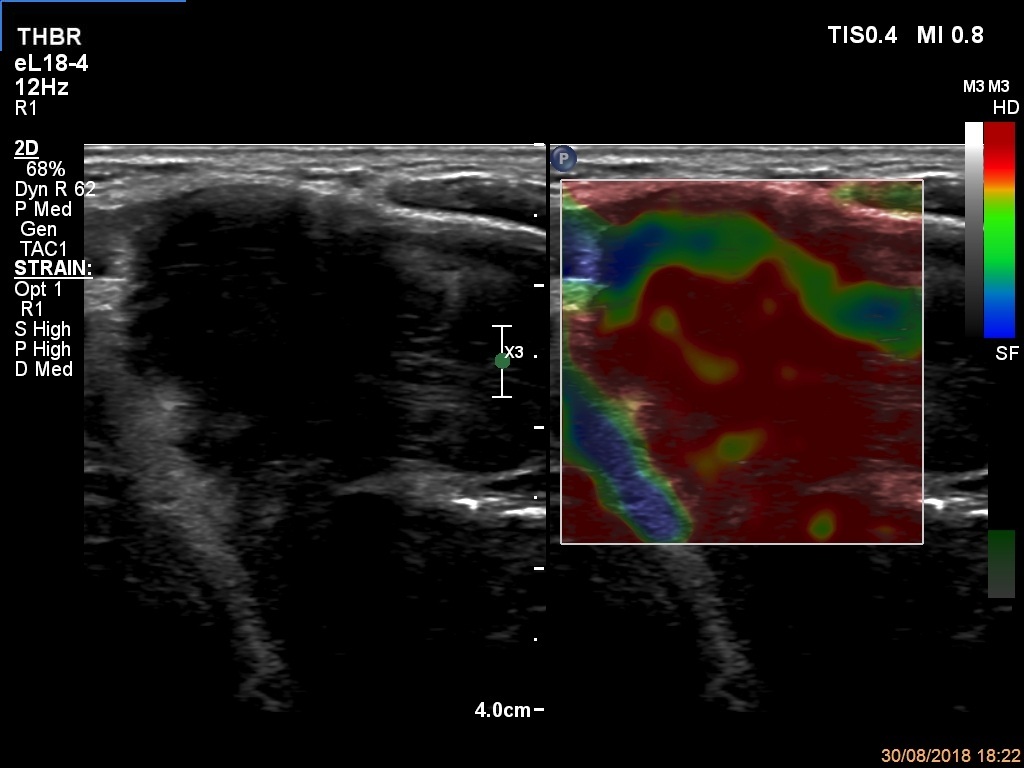

Ultrasonography. The thyroid was echonormal. There were a few hypoechogenic areas in the right lobe. There was a hypoechogenic mass with irregular shape in the left lobe. The lesion had echonormal fields and connective tissue. The microflow imaging revealed no intranodular vascularization while the lesion proved to be very hard on elastography.